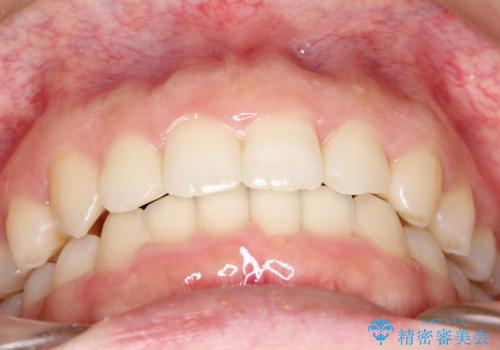

強い叢生がありましたが、抜歯は行わず上下顎ともに、主に歯列弓の拡大を行い叢生を改善しました。

見た目、嚙み合わせ及び、治療期間や施術内容に大変ご満足いただきました。